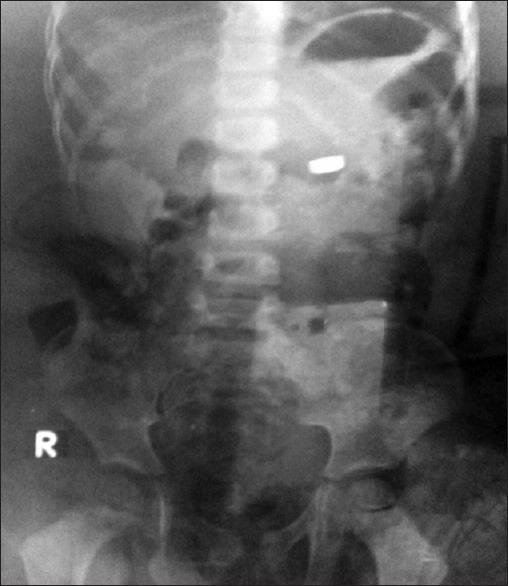

儿童摄入异物:两例报告

Two children were brought with history of battery ingestion. In one case, an emergency gastro intestinal endoscopy had to be done for the foreign body removal which was made up of corroded battery. In the other case, no interventation was undertaken & an uncorroded battery passed per anum along with stools after 15 days of ingestion.

两名儿童因吞食电池前来就诊。其中一例,因异物为腐蚀的电池,必须进行紧急胃肠内镜检查以取出异物。另一例未采取干预措施,吞食后15天,一枚未腐蚀的电池随粪便经肛门排出。